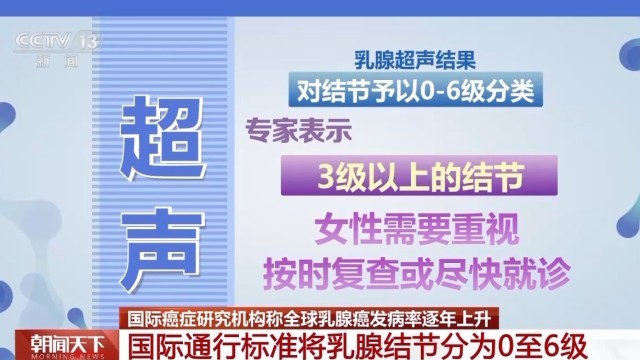

:(超声检查)首先是没有辐射,然后安全性好,所以不同年龄阶段的女性,年轻女性孕妇,还有需要频繁检查的女性都是可以经常做的。钼靶是一个X线检查,它是有辐射的,做的时候会把病人的乳房整个夹成一个片状,所以病人的耐受程度也会差一点。, 虽然超声没有辐射,但对于微小钙化,钼靶检查的敏感性更高。, , 根据国际通行的BI-RADS分级标准,对结节予以0至6级分类。专家表示,3级以上的结节,女性需要重视,按时复查或尽快就诊。,

, 根据国际通行的BI-RADS分级标准,对结节予以0至6级分类。专家表示,3级以上的结节,女性需要重视,按时复查或尽快就诊。, ,

:3级,一般半年要进行重复的超声检查;4级相对来讲恶性风险跨度比较大,一般建议要穿刺活检;5级的话就是高度怀疑恶性,所以一定要穿刺明确诊断,进行后续的治疗;6级就是已经在其他地方穿刺确诊为乳腺癌的病灶。,